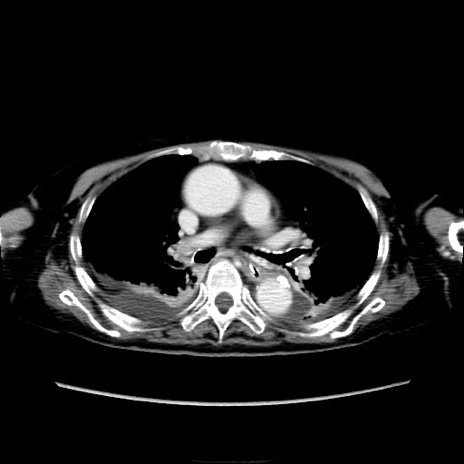

他院CT

横断像